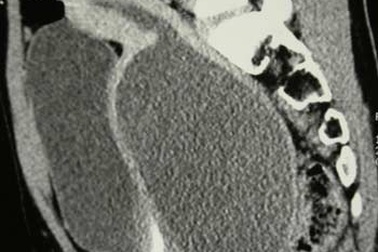

Phẫu thuật nội soi xử lý khuyết sẹo tử cung cho người phụ nữ 3 lần đẻ mổSau nhiều tháng đau bụng dữ dội và ra huyết kéo dài, chị Nguyễn Thị Trà (38 tuổi) được các bác sĩ BVĐK Vinmec Phú Quốc nội soi, xử lý khuyết sẹo mổ lấy thai - biến chứng sản khoa phổ biến nhưng điều trị phức tạp ở phụ nữ đẻ mổ nhiều lần.